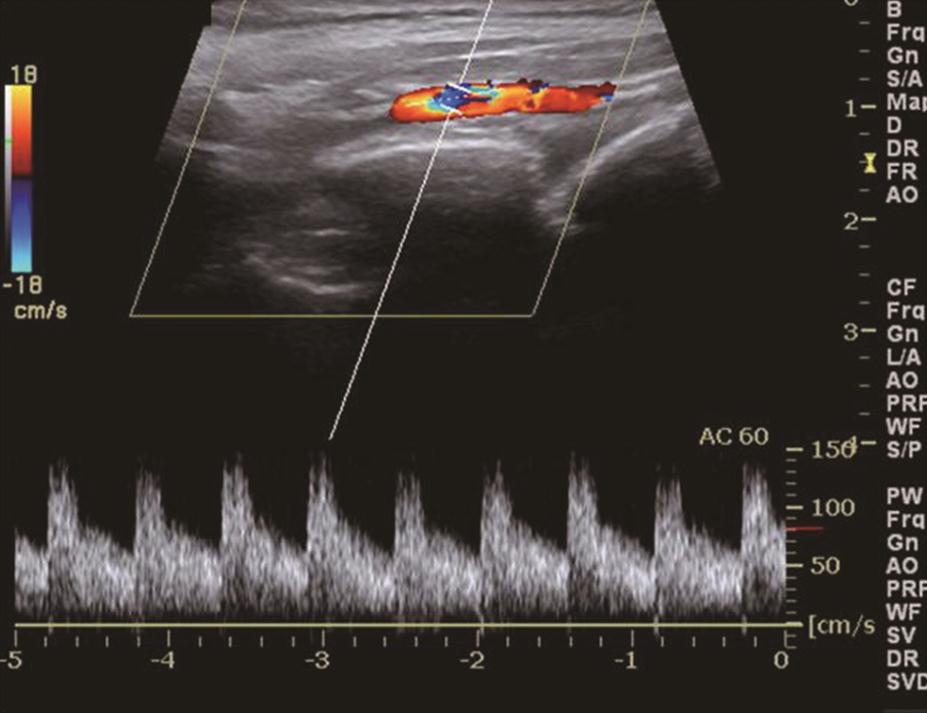

(五)Graves病

甲状腺呈弥漫性、对称性增大,包膜规则。腺体回声因病程和治疗情况而有所不同。未经治疗者,腺体回声均匀减低,少数呈散在、局灶性减低;病程长及反复发作者,腺体回声正常或稍强。腺体内可见多个管状无回声区(血管扩张)。彩色多普勒显示甲状腺内血流信号极为丰富,呈“火海征”(图3)。频谱多普勒可见甲状腺上、下动脉血流速加快,收缩期峰值流速多超过70cm/s(正常为30cm/s)(图4)。

图3右侧颈部纵切面:甲状腺右叶腺体血流信号丰富,呈“火海征”

图4与图3同一患者,右侧甲状腺上动脉收缩期峰值流速高达140cm/s